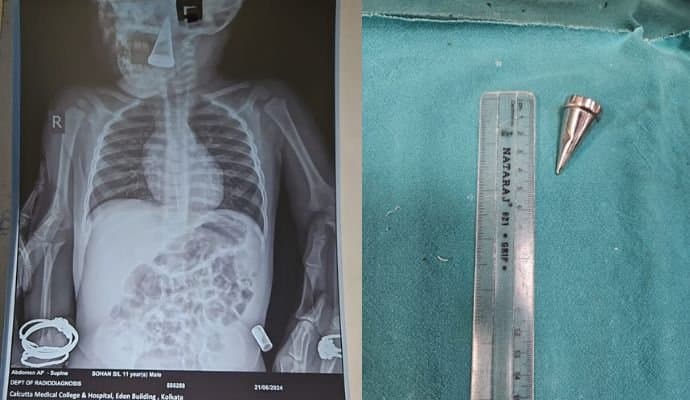

ব্যর্থ হয়ে এরপর হাসপাতালে নিয়ে আসেন শিশুটির অভিভাবকরা। ডা.অনিন্দ্য মিত্র বলেন, 'নি:শ্বাস নিতে কষ্ট হচ্ছিল বলে শিশুটির রক্তে অক্সিজেনের মাত্রা ধীরে ধীরে কমে যাচ্ছিল। শারীরিক অসুবিধার জন্য বাচ্চাটি খুব ছটফটও করছিল। অপারেশন থিয়েটারে তার হাতের শিরার মাধ্যমে ওষুধ ঢুকিয়ে তাকে আচ্ছন্ন করে ফরসেপের সাহায্যে ওই বস্তুটি বের করা হয়। অস্ত্রোপচারে প্রায় দেড় ঘণ্টা সময় লেগেছে। প্রাথমিকভাবে দেখে মনে হয়েছে জিনিসটি একটি ধাতব বস্তু।'